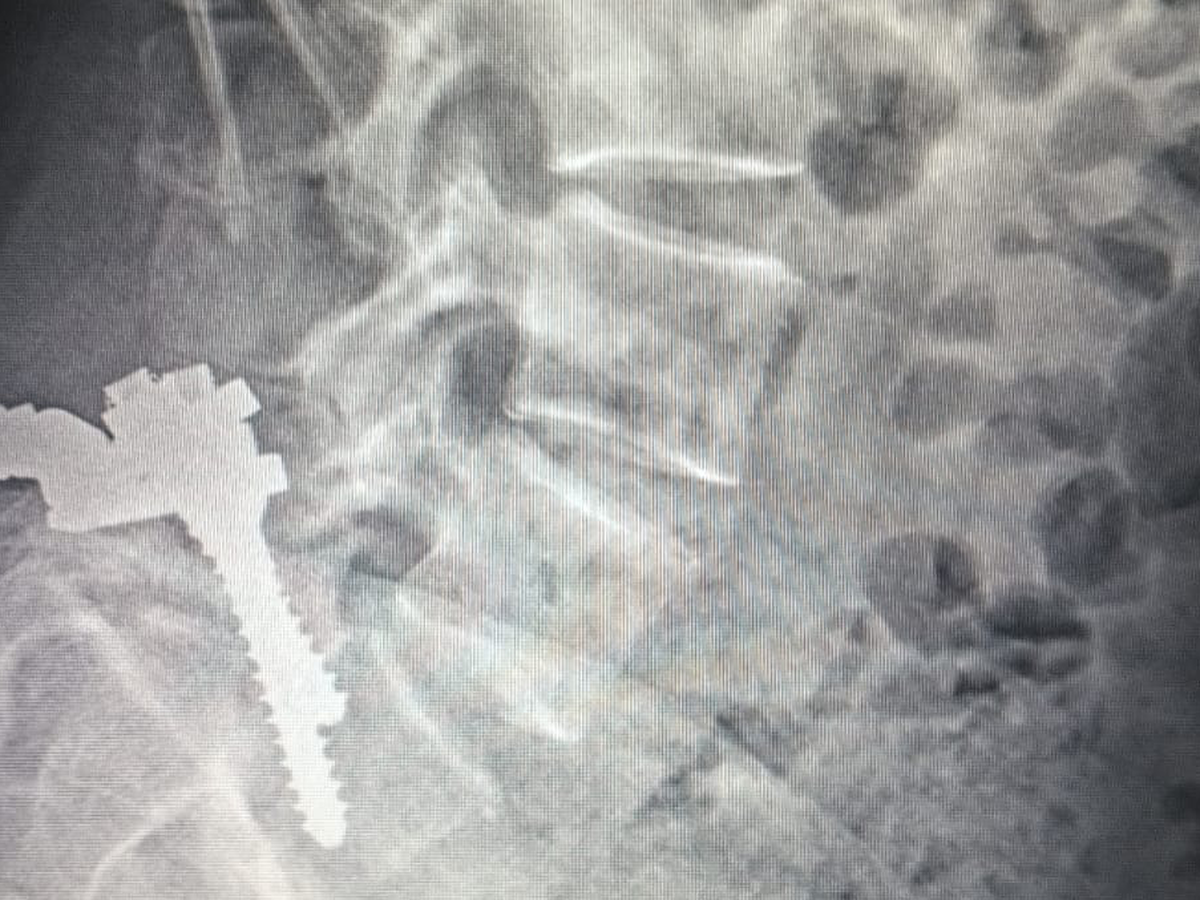

Hace 28 años, mi mamá fue operada de la columna y le colocaron prótesis de metal que, con el paso del tiempo, dejaron de ser funcionales. En los últimos meses, su condición ha empeorado: presenta dolor constante, adormecimiento en las piernas, mareos y una dificultad cada vez mayor para caminar, sentarse y descansar.